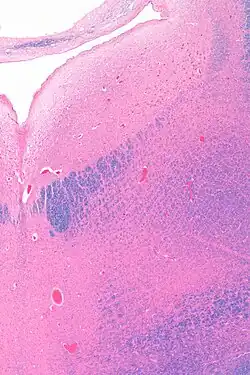

Anatomy

The locus coeruleus (LC) is located in the posterior area of the rostral pons in the lateral floor of the fourth ventricle. It is composed of mostly medium-size neurons. Melanin granules inside the neurons contribute to its blue colour. Thus, it is also known as the blue nucleus, or the nucleus pigmentosus pontis (heavily pigmented pontine nucleus).[5] The neuromelanin is formed by the polymerization of norepinephrine and is analogous to the black dopamine-based neuromelanin in the substantia nigra.